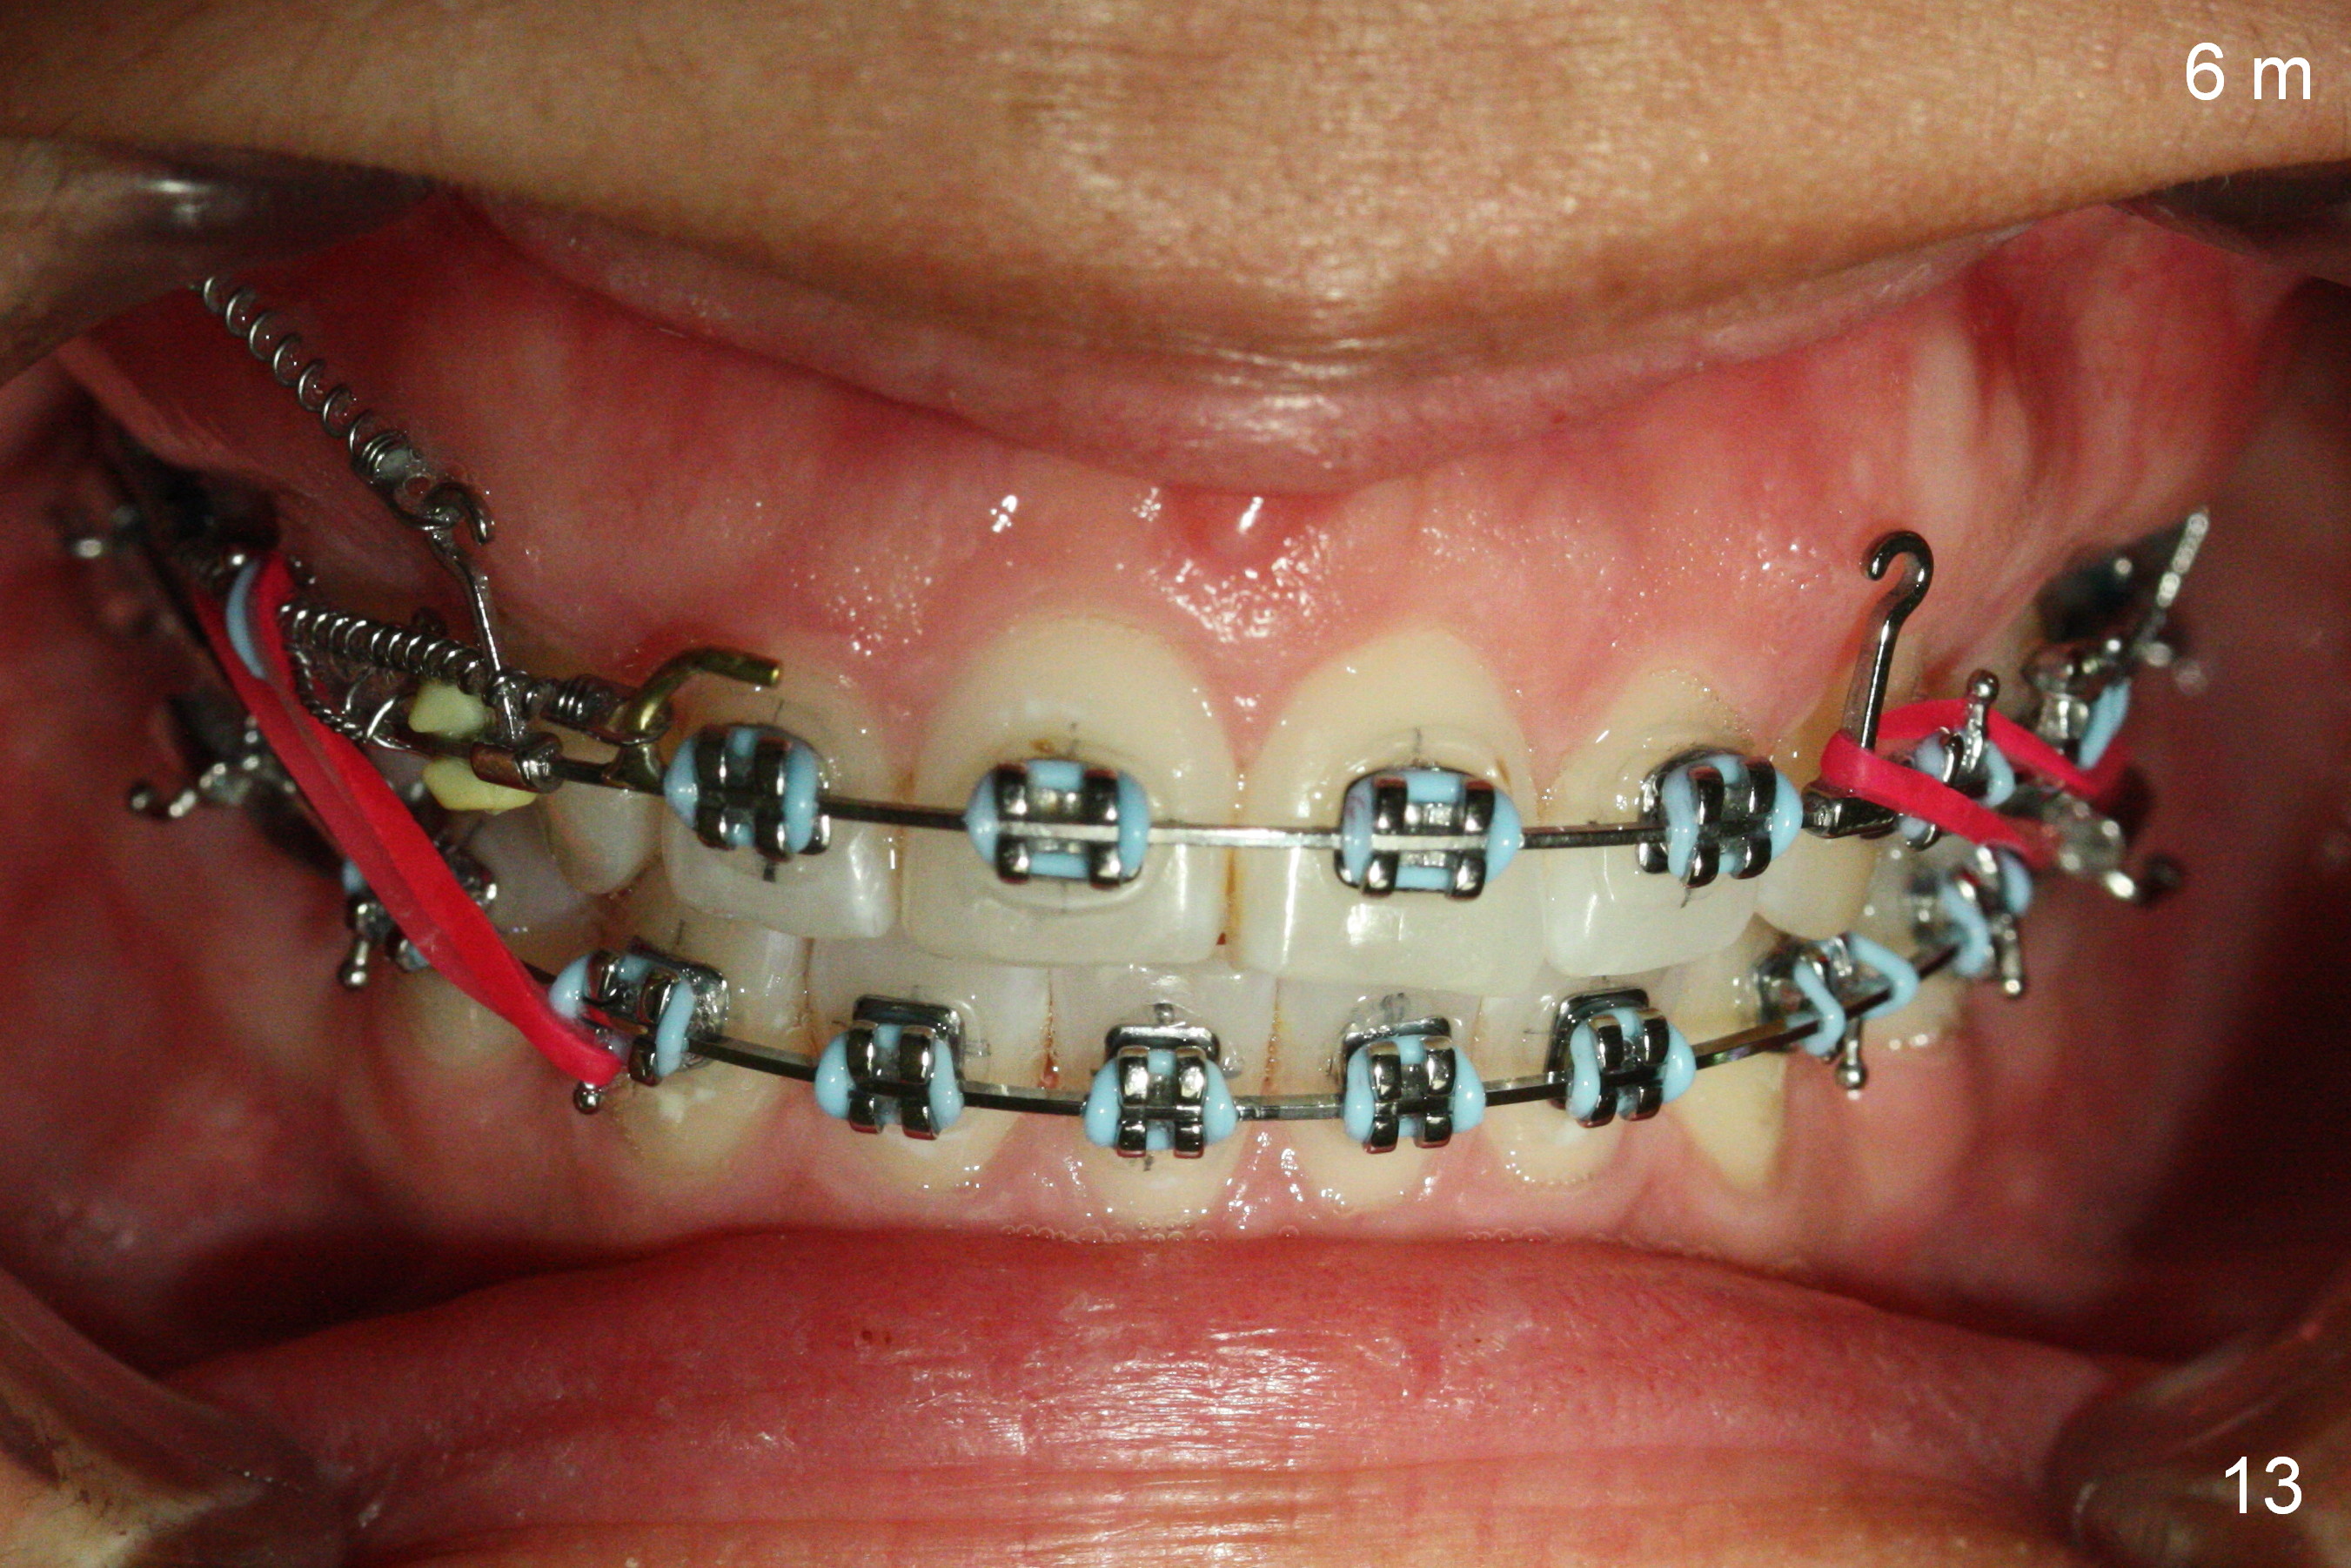

Six months post zygomatic implants, the profile, anterior overbite and overjet and the right posterior interdigitation are within normal limit (Fig.11), whereas the left one not (Fig.12).  The lower midline appears to be deviated to the left.  Elastics are used for correction (Fig.11,13,14).  A second option is to reduce the number of closed springs on the right and increase the one on the left.